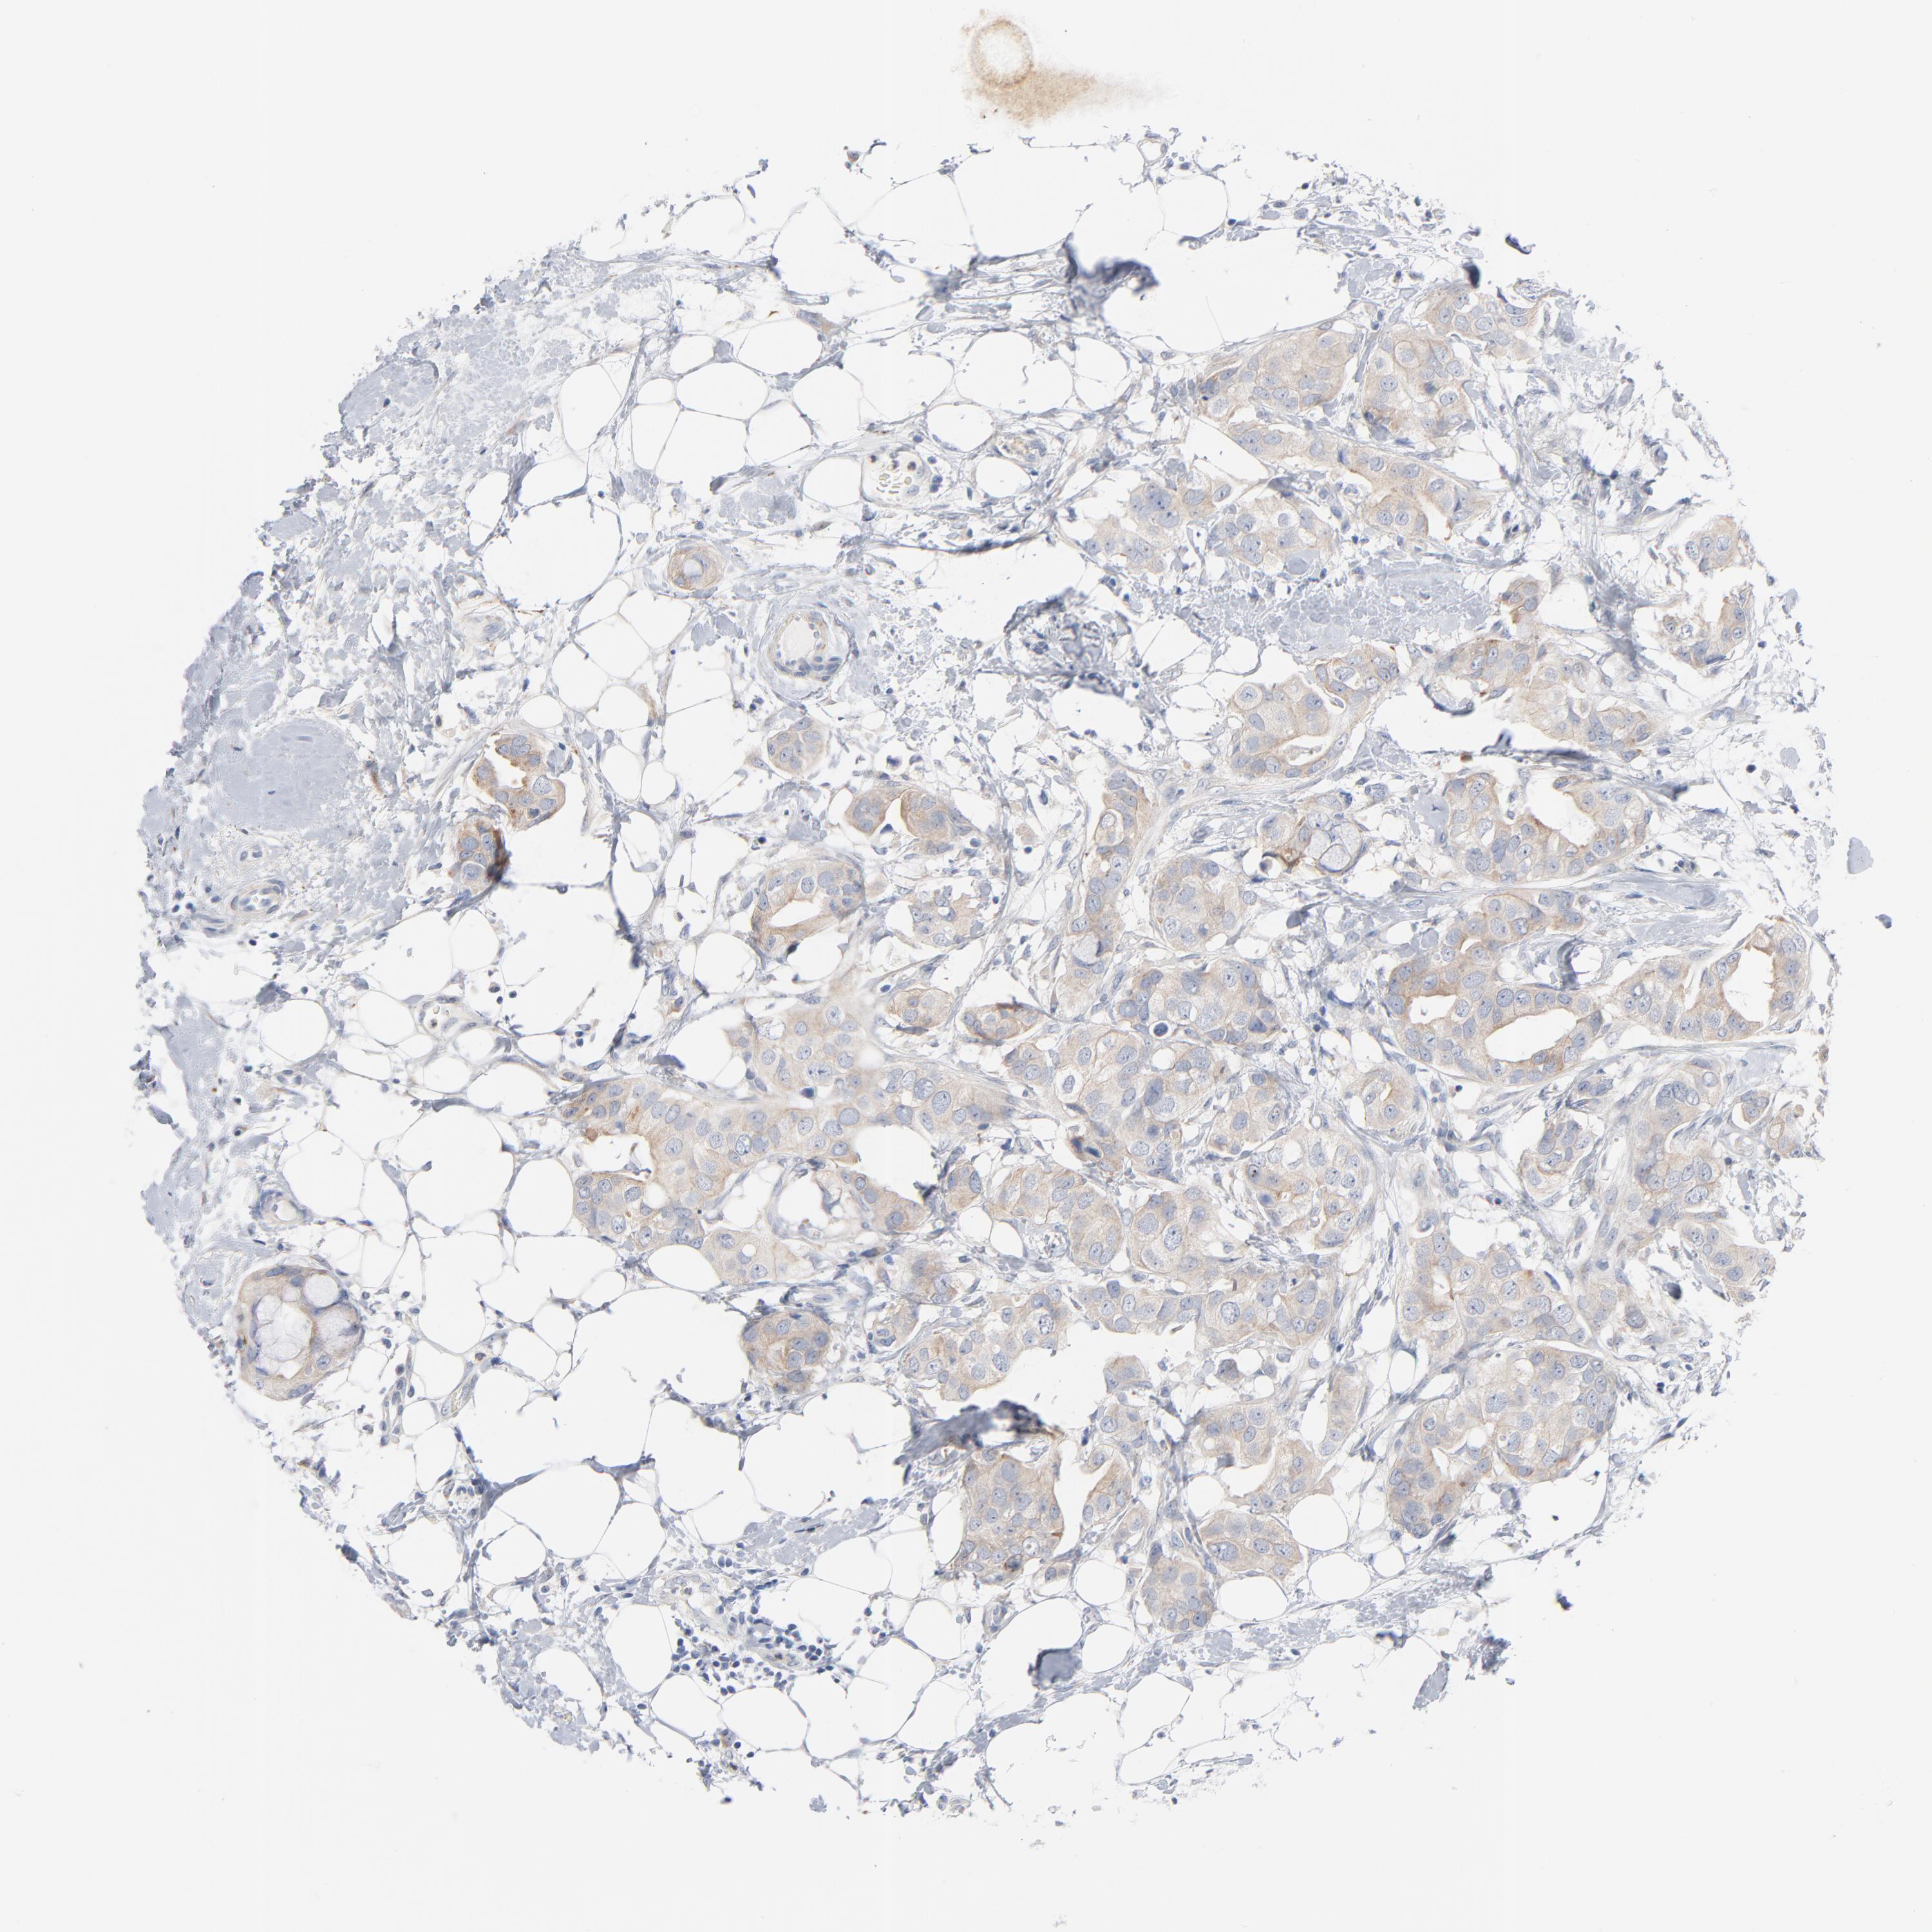

CANCER BREAST CANCER Show tissue menu

BRCA TCGA BRCA VALIDATION PROTEIN EXPRESSION

ANTIBODIES

AND

VALIDATION